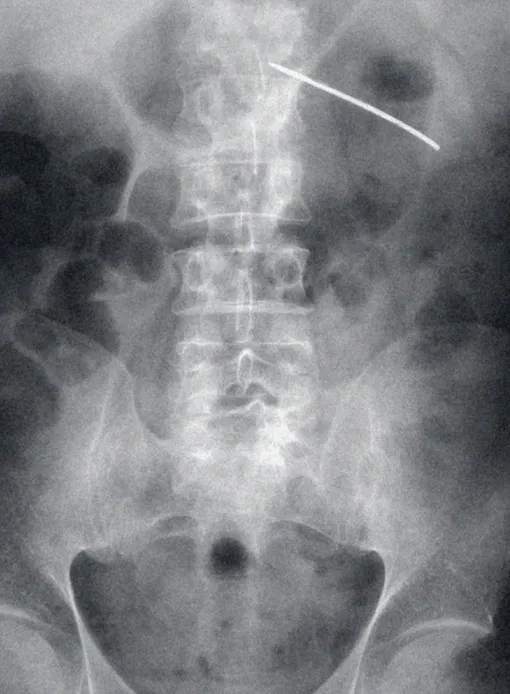

ЮАР, 1993 ГОД

Нижняя часть тела мужчины с фрагментом иглы в области левой почки. Иглы вгоняют через спину жертвы, повреждая внутренние органы. Толстая игла прошла в брюшную полость и почти достигла левой почки, после чего сломалась. К счастью, она не проткнула брюшную плевру, что могло вызвать кровоизлияние, поэтому жертве удалось выжить.